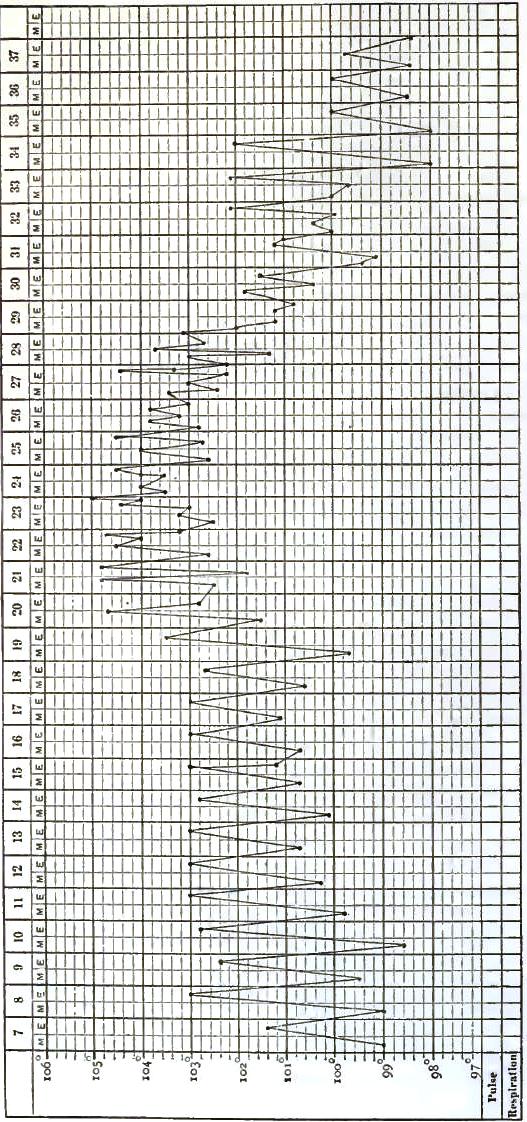

| 12. | CHART OF TYPICAL RANGE OF TEMPERATURE IN TYPHOID FEVER, AFTER WUNDERLICH |

| 13. | CHART SHOWING RECRUDESCENCE OF FEVER FROM INDISCRETION OF DIET |

| 14. | CHART SHOWING FALL OF TEMPERATURE FROM INTESTINAL HEMORRHAGE IN TYPHOID FEVER |

| 15. | PULSE-TRACING IN RELAPSES OF TYPHOID FEVER |

| 16. | CHART OF TEMPERATURE IN TYPHOID FEVER WITH RELAPSE.—ORIGINAL ATTACK |

| 17. | CHART OF TEMPERATURE IN TYPHOID FEVER WITH RELAPSE.—RELAPSE |

| 18. | TEMPERATURE CHART OF TYPHOID FEVER.—ABORTIVE ATTACK, FOLLOWED BY TYPICAL ATTACK |